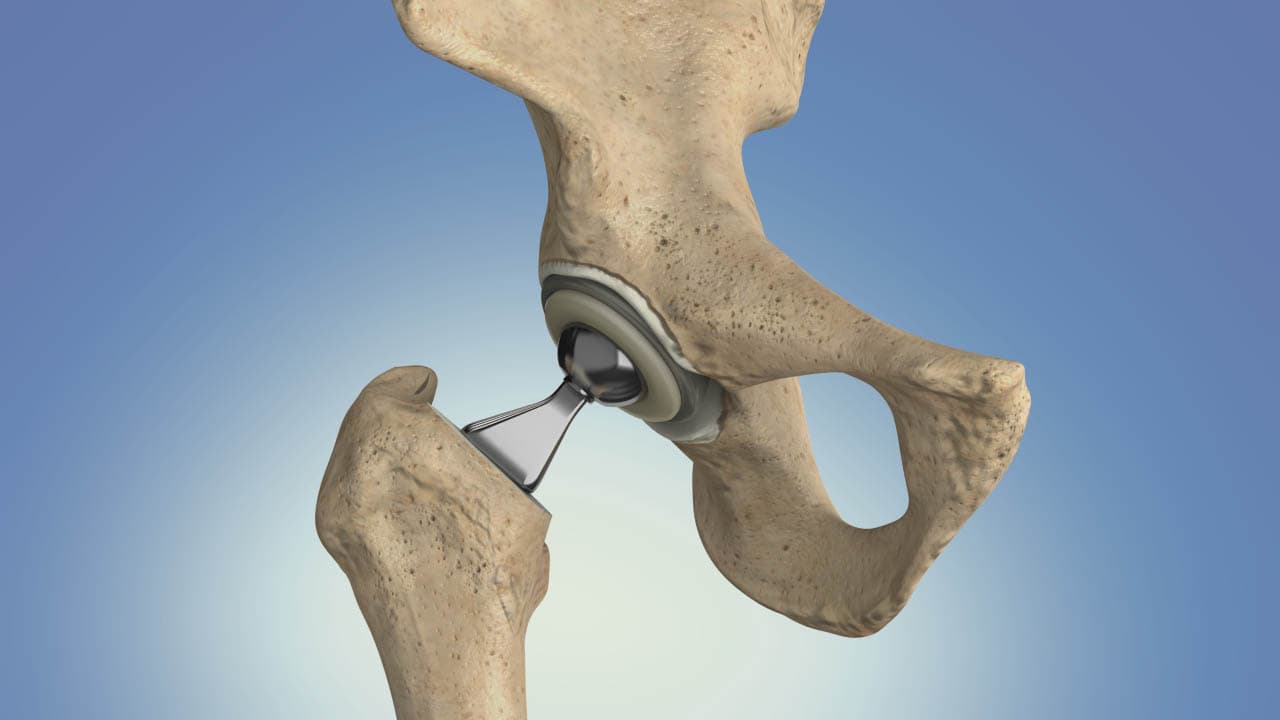

There are two main types of hip replacement surgery: total hip replacement (THR) and partial hip replacement. In a total hip replacement, both the acetabulum (the hip socket) and the femoral head (the ball of the thigh bone) are replaced. In a partial hip replacement, only the femoral head is replaced. The choice between these procedures depends on the patient's specific condition and the extent of joint damage.

The surgery typically involves making an incision over the hip joint, dislocating the hip to gain access to the damaged area, and then carefully removing the diseased tissue. The prosthetic components are then implanted and secured in place, often using bone cement or a press-fit technique that encourages natural bone growth around the implant. The procedure usually takes a few hours and is performed under general or regional anesthesia.

Partial hip replacement, also known as hemiarthroplasty, involves replacing only the damaged femoral head (the ball of the thigh bone) while leaving the acetabulum (hip socket) intact. This type of surgery is typically recommended for patients with specific conditions such as a fractured femoral neck, where only the femoral head is affected. Partial hip replacement tends to have a shorter surgical time and recovery period, as it involves less extensive modifications to the hip joint. However, it is generally not suitable for patients with extensive arthritis or significant acetabular damage.

Total hip replacement (THR), on the other hand, involves replacing both the femoral head and the acetabulum with prosthetic components. This comprehensive approach is often necessary for individuals suffering from severe osteoarthritis, rheumatoid arthritis, or other degenerative conditions that affect both parts of the hip joint. During a total hip replacement, the surgeon removes the damaged cartilage and bone from both the femoral head and the acetabulum, replacing them with artificial components made of metal, ceramic, or plastic. The prosthetic components are designed to mimic the natural movement of the hip joint, providing significant pain relief and improved mobility.

Total hip replacement surgery involves the use of various materials to create prosthetic components that replace the damaged parts of the hip joint. These materials are carefully selected for their durability, biocompatibility, and ability to replicate the natural movement of the hip. The primary components of a total hip replacement include the femoral stem, femoral head, acetabular cup, and a liner that fits within the acetabular cup.

The femoral stem, which is implanted into the thigh bone (femur), is typically made of metal alloys such as titanium or cobalt-chromium. Titanium is favored for its lightweight nature, strength, and excellent biocompatibility, allowing it to integrate well with the surrounding bone. Cobalt-chromium alloys are known for their high wear resistance and strength, making them suitable for the demanding environment of the hip joint.

The femoral head, which replaces the ball of the thigh bone, can be made of either metal or ceramic. Ceramic femoral heads are becoming increasingly popular due to their smooth surface, which reduces friction and wear against the acetabular cup. Metal femoral heads, often made of cobalt-chromium, are also commonly used for their durability and wear resistance.

The acetabular cup, which replaces the hip socket, is usually made of metal alloys such as titanium or cobalt-chromium. To reduce wear and provide a smooth articulation surface, the acetabular cup is often lined with a polyethylene (plastic) liner or a ceramic liner. Highly cross-linked polyethylene liners have improved wear resistance compared to traditional polyethylene, making them a popular choice for hip replacements.